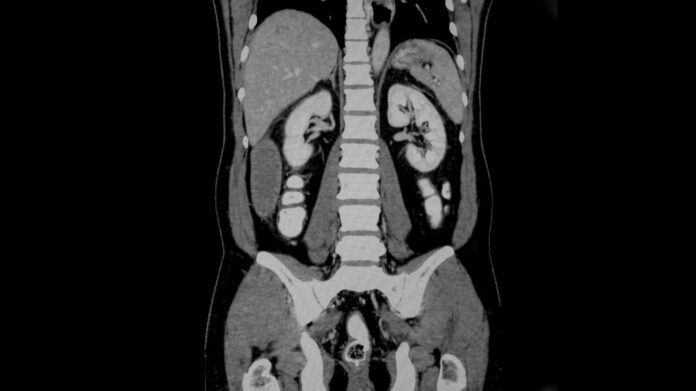

Компьютерная томография (КТ) — не инвазивный рентгенологический метод исследования, предназначенный для просмотра внутренних структур организма и их изменений с помощью рентгеновских лучей. Отметим, если вас интересует подготовка к КТ брюшной полости с контрастированием, то прошу посетить данный сайт. КТ является более точным исследованием, чем простой рентген – во время осмотра исследуемая область сканируется тонкими слоями, благодаря чему врач может с большой точностью определить очаги поражения и их распространение.

КТ обычно используется для получения точной и подробной информации об измененных структурах органов и тканей: нарушениях мозгового кровообращения, множественных травмах грудной клетки, живота, легких, костей, сердечно-сосудистых заболеваниях, заболеваниях позвоночника, состоянии внутренних органов, опухолях и их распространение плотность костной ткани.